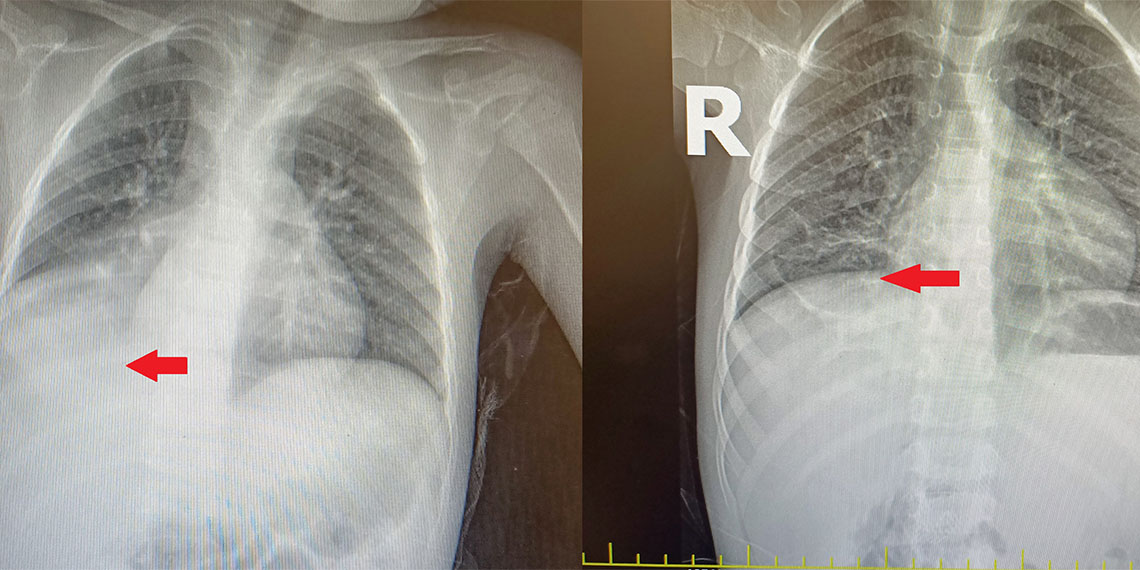

Çekilen röntgen ve tomografisinde, sağ akciğerin neredeyse yarısının tamamen çökmüş olduğu görüldü. Çocuk Cerrahi hekimlerinin dikkati sayesinde, yıllar önce yabancı cisim yuttuğu anlaşılan çocuğun 3 yıl boyunca nefes borusunda karpuz çekirdeği ile yaşadığı anlaşıldı. Küçük Abdullah, girişimsel bir işlem olan bronkoskopi ile ameliyata gerek kalmadan sağlığına kavuşturuldu. Doktorları, nefes borusunda bu kadar uzun süre yabancı cisimle yaşayan bir hastanın, ‘ameliyata gerek kalmadan’ tedavi edilebilmesinin literatürde nadiren görüldüğünü, bu vakanın kendilerini de şaşkına çevirdiğini kaydetti.

Sağ akciğerin neredeyse yarısının sıvıyla dolduğu anlaşılınca, Çocuk Cerrahi Kliniği’nin de görüşüne başvuruldu. Hekimlerin dikkati sayesinde çekilen tomografi sonrası, küçük Abdullah’ın nefes borusuna yıllar önce yabancı cisim kaçtığı anlaşıldı. 3 yıl boyunca nefes borusunda karpuz çekirdeği ile yaşayan Abdullah, üzerinden bu kadar uzun zaman geçmiş olmasına rağmen, girişimsel bir işlem olan bronkoskopi ile ameliyata dahi gerek kalmadan sağlığına kavuşturuldu. Çocuk Cerrahi Kliniği’nden Opr. Dr. Mehmet Çakmak ile Çocuk Göğüs Hastalıkları Uzmanı Dr. Mustafa Eres, nefes borusunda bu kadar uzun süre yabancı cisimle yaşayan bir hastanın, “ameliyata gerek kalmadanö tedavi edilebilmesinin literatürde nadiren görüldüğünü, bu vakanın kendilerini de şaşkına çevirdiğini kaydetti.

Başakşehir Çam ve Sakura Şehir Hastanesi Çocuk Cerrahi Kliniği’nden Opr. Dr. Mehmet Çakmak, “Acil servisteki doktor arkadaşlarımızın muayenesi sonrası çekilen akciğer röntgeninde, sağ alt bölgede sıvı birikimi nedeniyle bize danıştılar. Hastanın öyküsünü annesinden tekrar dinlediğimizde, şikayetlerinin 1 yaşında kardeşleriyle otururken karpuz çekirdeğini ağzına götürmesi sonrası başladığını öğrendik. O zaman çekilen akciğer röntgeninde herhangi bir patolojik bulguya rastlanmayınca, 3 yıl boyunca semptomlarının ara ara iyileşmesi nedeniyle de daha çok astım, bronşit pnömoni gibi teşhisler düşünülmüş ve buna yönelik tedaviler verilmiş. Çünkü normalde yabancı cisim aspirasyonlarında, semptomlar gerilemez. Biz, annesinin verdiği öyküyü dinleyince tomografi çektik ve sağ akciğer alt bölgeyi havalandıran bronşun, bir yabancı cisimle tıkalı olduğunu tespit ettik. Yaptığımız bronkoskopide bir karpuz çekirdeğine rastladık ve işlem esnasında karpuz çekirdeğini çıkardık” dedi.